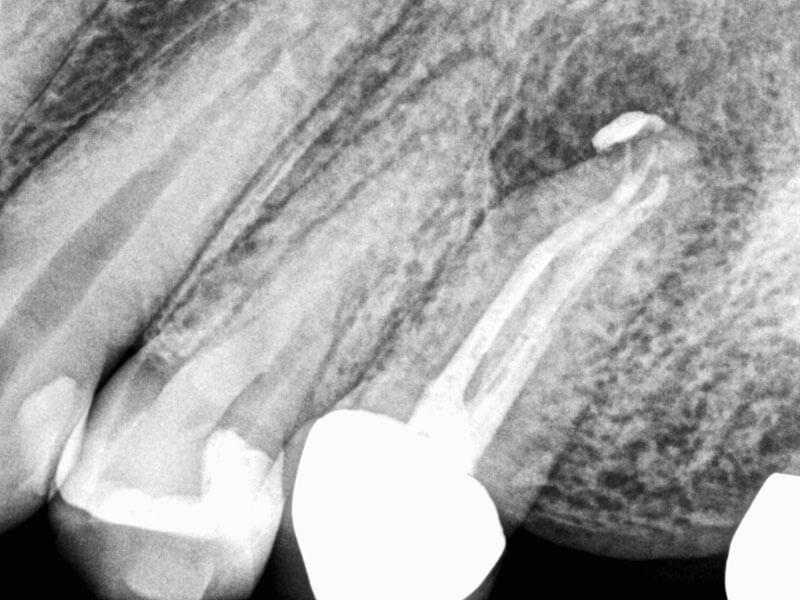

Retreat

Nestor Cohenca, DDS, FIADT

View Case Images